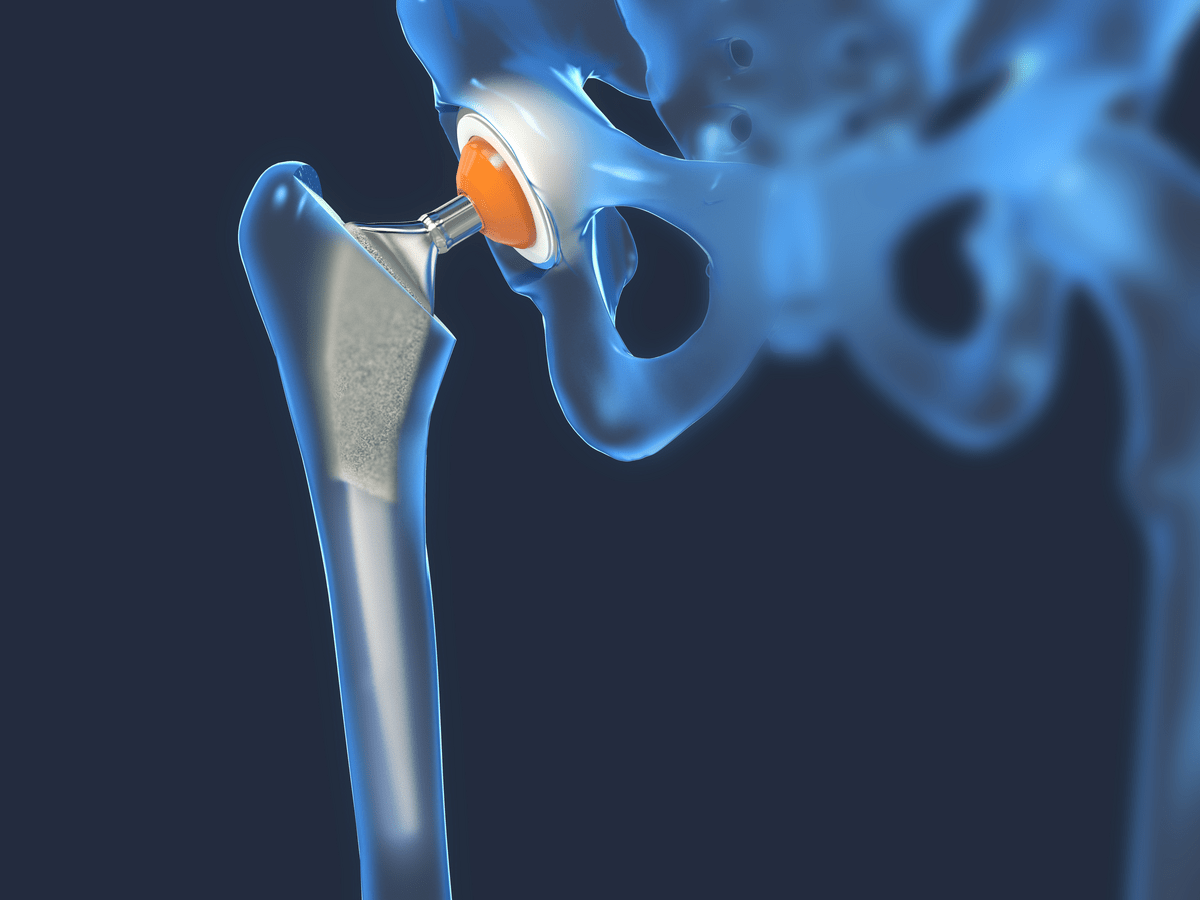

Total Hip Replacement Surgery

When you choose Riverside for your orthopedic care, you have the support of an entire team of fellowship-trained orthopedic surgeons, board-certified anesthesiologists, certified nurse practitioners and specialized orthopedic physical therapists to help you improve your health.

Total Hip Replacement

Learn about the anatomy of the hip and how a total hip replacement is performed.

Function of a hip replacement surgery is in frontal view -